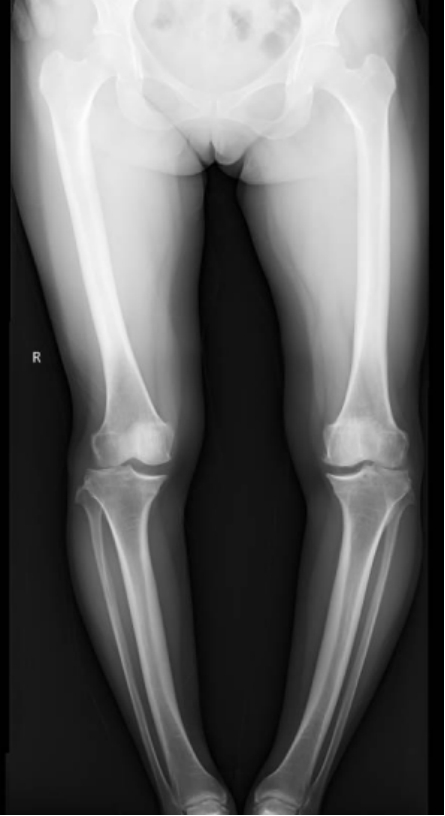

李彬在詳細(xì)了解了董阿姨的病史、進(jìn)行了全面的體格檢查和相關(guān)的輔助檢查后,組織科室進(jìn)行了深入的討論。最終的“答案”是——雙膝骨性關(guān)節(jié)炎、雙膝關(guān)節(jié)畸形、骨質(zhì)疏松以及雙膝半月板損傷。

面對(duì)這樣復(fù)雜且嚴(yán)重的病情,李彬并沒有退縮。他深知,對(duì)于董阿姨來說,這不僅僅是一次手術(shù),更是一次重生的機(jī)會(huì)。因此,他精心制定了手術(shù)方案:對(duì)雙下肢脛骨近端、遠(yuǎn)端以及雙側(cè)腓骨遠(yuǎn)端進(jìn)行截骨矯形,并進(jìn)行植骨內(nèi)固定。這樣的手術(shù)方案,無疑是對(duì)醫(yī)生技術(shù)的一次高難度挑戰(zhàn)!

手術(shù)前 手術(shù)后